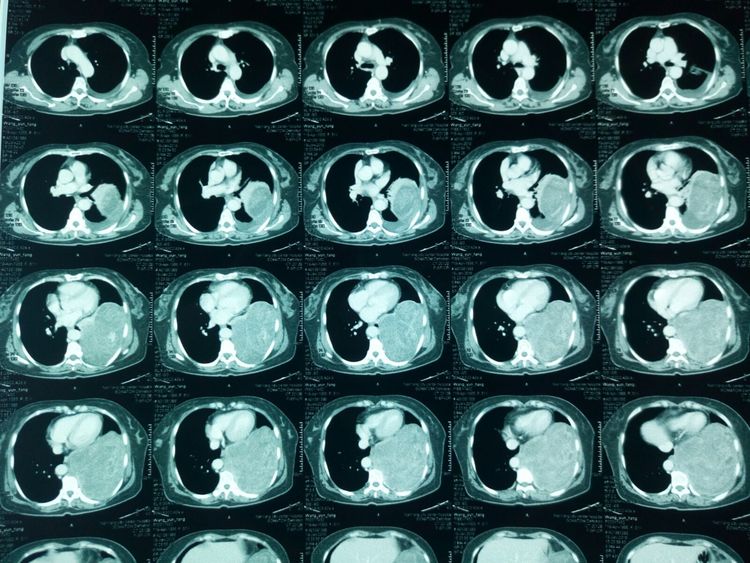

入院胸部ct,提示肿瘤直径约17*15*10cm,占据胸腔一半以上空间。

肿瘤与胸主动脉、下肺静脉等大血管关系密切。